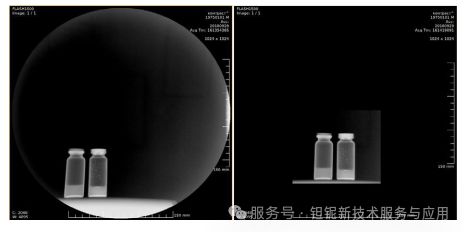

制备的稀土TaO₄纳米颗粒呈准球形,粒径分布 20-50 nm,虽存在团聚现象,但在二甲基甘油硅基质中分散均匀(图 16、图 17)。

图17.含有液体样品的玻璃瓶的射线照相:左边是蒸馏水,底部和壁上含有不溶于水的不透射线物质颗粒。